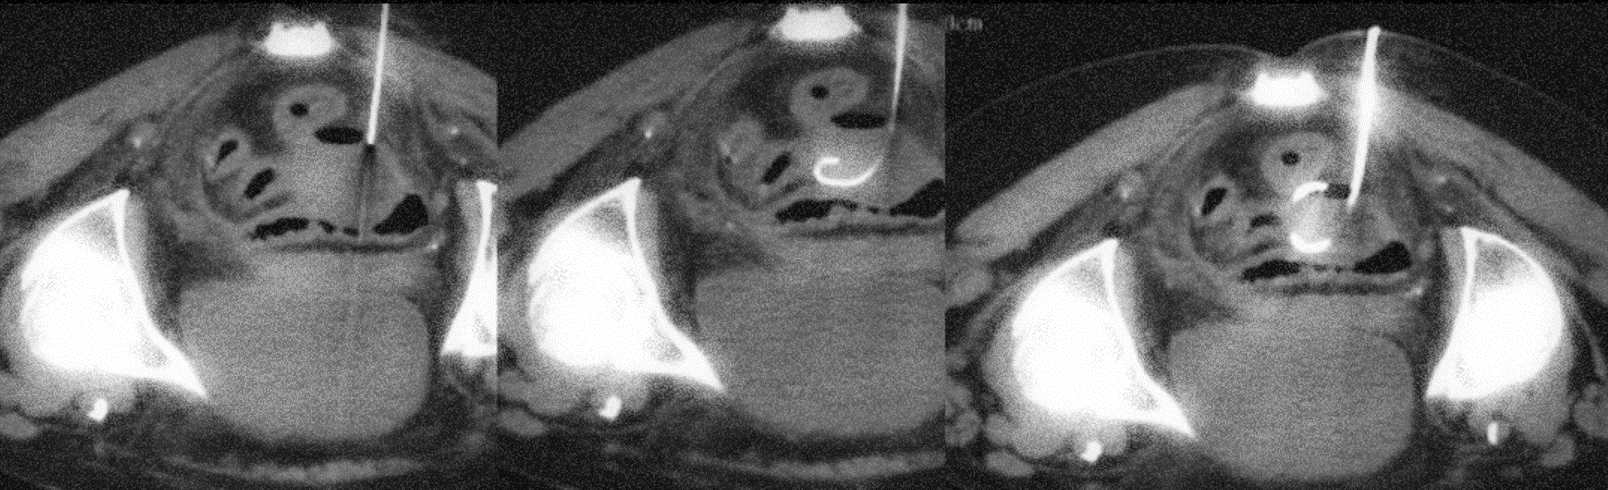

- Insertion du drain : Une aiguille fine servant à réaliser l’anesthésie locale est insérée sous guidage radiologique pour accéder à la zone où le fluide est accumulé. Tout le trajet d’accès est anesthésié. Une fois l’anesthésie locale réalisée, on met en place sous guidage radiologique une aiguille de plus large diamètre qui nous permettra d’insérer le drain (tube creux souple) afin de permettre l’évacuation du liquide. Selon la situation, ce drain peut être laissé en place pendant quelques jours voire semaines.

- Imagerie médicale : Le radiologue interventionnel va choisir la technique d’imagerie (échographie, scanner) qui lui permettra de localiser avec précision la zone à drainer et de pouvoir guider le plus précisément possible l’aiguille permettant d’amener le drain à la collection. Pour les collections profondes, le scanner est généralement utilisé avec un contrôle itératifs de la progression de l’aiguille. Pour les collection plus superficielles, l’échographie est souvent la technique de guidage la plus utilisée car elle permet de suivre en temps réel l’avancée de l’aiguille .

- Contrôle final et fixation des drains: Des images radiologiques sont prises pour s’assurer que le drain est correctement positionné. Le drain est alors fixé à la peau par des points de sutures afin d’éviter d’être accidentellement retiré lors des mouvements du patient. Le drain est ensuite raccordé à une poche afin de sécuriser l’évacuation.